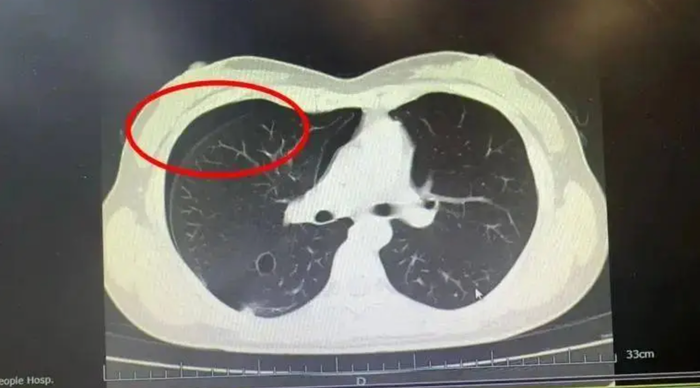

Ngay lập tức, cô được đưa đến khoa Hô hấp của Bệnh viện Nhân dân số 3, quận Dư Hàng. Bác sĩ Hà Lập Hàng, sau khi kiểm tra CT ngực, chỉ có thể lắc đầu và thông báo: "Phổi của cô bị ‘nổ’ rồi! Cô mắc chứng tràn khí màng phổi tự phát. Cần nhập viện ngay để thực hiện chọc hút khí và đặt ống dẫn lưu".

Kết quả chụp CT cho thấy người phụ nữ bị tràn khí màng phổi tự phát. (Ảnh: Sohu)